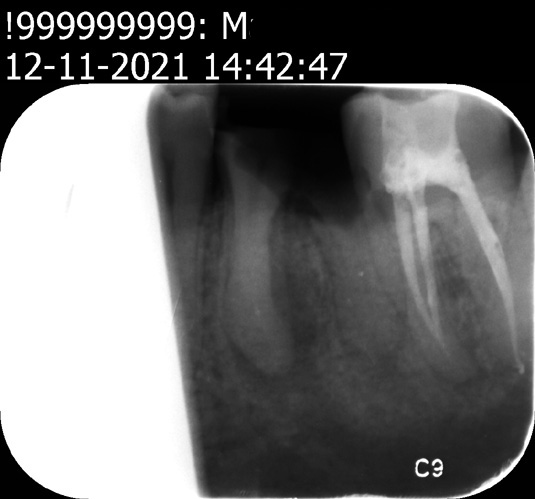

- Naast element 37 waar 90 staat , de weledegeleerde tandarts Andre Padrao een wortelkanaalbehandeling in ziet ,was een vlekje . Dit kan ik nu nog bewijzen want er is niet geboord of niets. De weledelgeleerde tandarts Padrao kreeg de originele foto ter beschikking op 07-10-2021 hij zag hier er een wortel kanaal behandeling in

Foto 0 . 24-02-2021 is gemaakt door tandarts Baeten is niet geschikt om te oordelen of er twee wortelkanaal behandelingen nodig zijn

Ondanks alles heb ik toch veel aan de second opinions gehad . De begroting op 7-10-2021 is gebaseerd op foto 0 gemaakt op 24-02-2021 door tandarts Baeten . Deze foto is niet geschikt volgens de twee tandartsen boven zou er eerst een detail foto moeten worden gemaakt . volgens de e-mail van Juul op 20-01-2022 heeft de weledelgeleerde tandarts Padrao de begroting gemaakt op 07-10-2021.

Op deze foto ziet hij twee wortel punt /per apicaal ontstekingen . Juul heeft tijdens ons gesprek op 07-10-2021 met de achterkant van een instrument op element 36 & 37 getikt . Het abces deed ontzettend pijn maar er was niets geen pijn aan de kiezen.

| foto (24-02-2021) Hierop is de wortelkanaal behandeling van de weledelgeleerde tandarts Andre Padrao gebaseerd |

Hier had de weledelgeleerde tandarts Padrao volgens de twee secon opinons een detail foto moeten maken |

foto 1 (21-10-2021) foto2 (21-10-2021) foto3 (12-11-2021) foto 4 (12-11-2021)